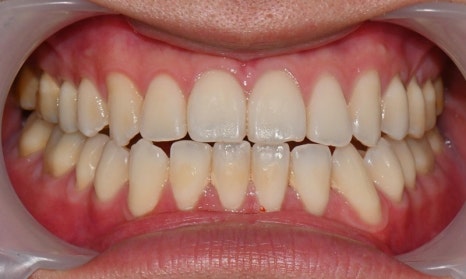

아래 앞니에 남아있는 레진 제거 후 미백 치료 결과

예전에 교정 치료를 마치고 미백을 하러 오시는 환자들을 보면, 가끔 브라켓을 뗀 이후 레진 접착제가 치아 표면에 일부 남아 있어서 그 부분이 노랗게 변색된 경우를 발견할 수 있습니다. 교정을 끝내고 브라켓을 제거한 이후에 레진 접착제를 깨끗하게 제거한 후 폴리싱을 해서 매끈하게 해주어야 하는데, 그렇지 못할 경우 남아있는 접착제에 의해 주변에 치태가 침착되거나 착색이 증가할 수 있고, 남아있는 레진이 변색될 수 있습니다. 이 경우 남아있는 레진을 제거한 후 미백을 해주게 되면 깨끗한 치아를 얻을 수 있습니다.